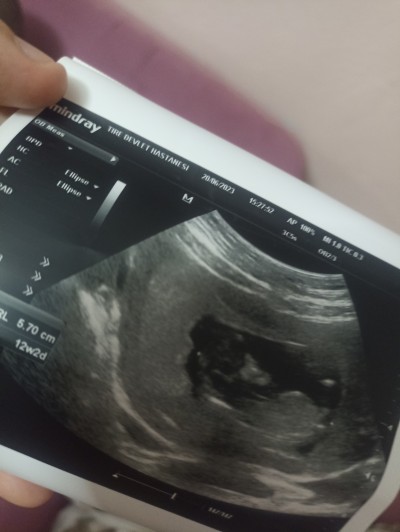

Kızlar ultrasondan anlıyorsanız bakar mısınız? Çok merak ediyorum doktor söyledi ama net değil benzettim dedi sadece . Sizin fikrinizi de merak ediyorum ☺️

Gebelik haftası 12+5

Erkeğe mi benzetti

Evet öyle geldi erkek bebek cinsiyetini erken gösteriyor bir de burda arkadaşlar yazmıştı kese darsa erkek bebek diye ondan tahmin ettim canım